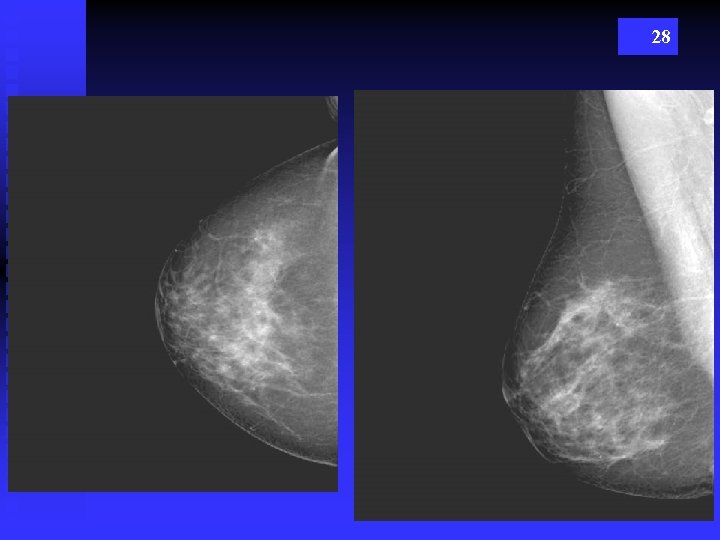

28